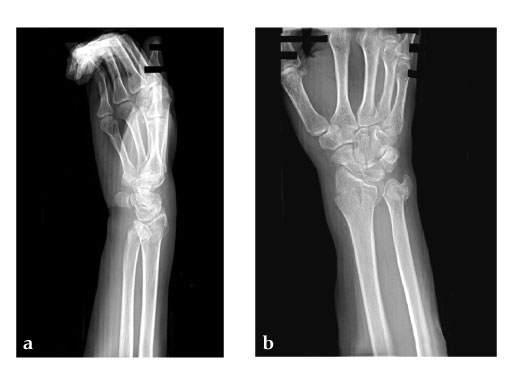

28-year-old woman.

Fig 3ab: X-rays postoperative.